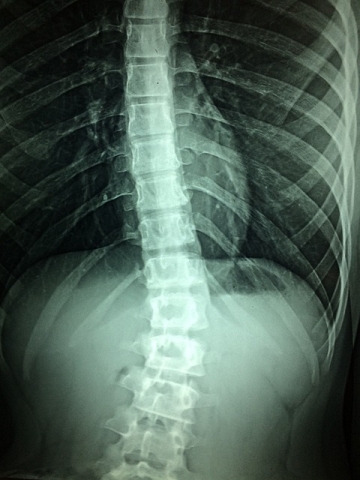

29일간의 연구 기간 동안 참가자들은 촉수 양쪽에 있는 허리 부위에 삽입된 두 개의 척수 자극(SCS) 전극을 이식 받았으며, 자극은 전적으로 감각 신경근으로 향하게 했다. 테스트 세션은 각각 4시간 동안 진행됐으며, 자극 장치가 제거될 때까지 총 19세션 동안 주 5회 실시됐다.